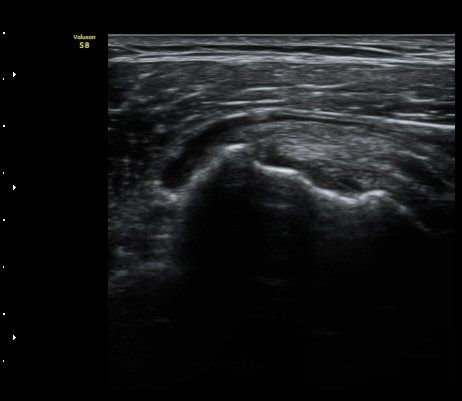

3°³¿ù ÈÄ ÃßÀû°Ë»ç

2049205267_e81a53aa_US181338113.jpg